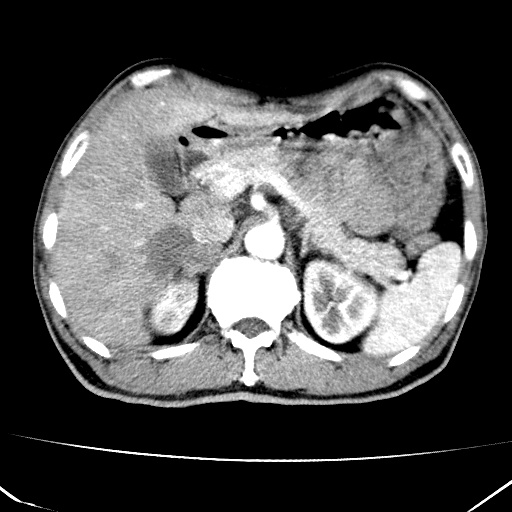

肝脏多发类圆形低密度影,考虑肝脏转移瘤,肝胃韧带一淋巴结肿大,原发?胃癌?

考虑胃癌并肝脏及腹膜后淋巴结转移;不排除淋巴瘤。

肝内转移瘤,腹腔及腹膜后淋巴结转移。